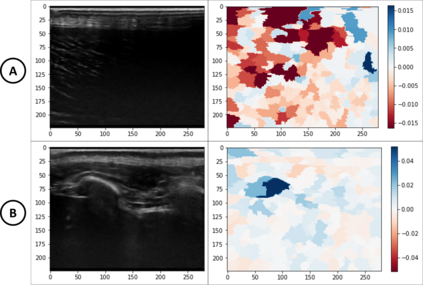

Approximately 1.25 million people in the United States are treated each year for burn injuries. Precise burn injury classification is an important aspect of the medical AI field. In this work, we propose an explainable human-in-the-loop framework for improving burn ultrasound classification models. Our framework leverages an explanation system based on the LIME classification explainer to corroborate and integrate a burn expert's knowledge -- suggesting new features and ensuring the validity of the model. Using this framework, we discover that B-mode ultrasound classifiers can be enhanced by supplying textural features. More specifically, we confirm that texture features based on the Gray Level Co-occurance Matrix (GLCM) of ultrasound frames can increase the accuracy of transfer learned burn depth classifiers. We test our hypothesis on real data from porcine subjects. We show improvements in the accuracy of burn depth classification -- from ~88% to ~94% -- once modified according to our framework.